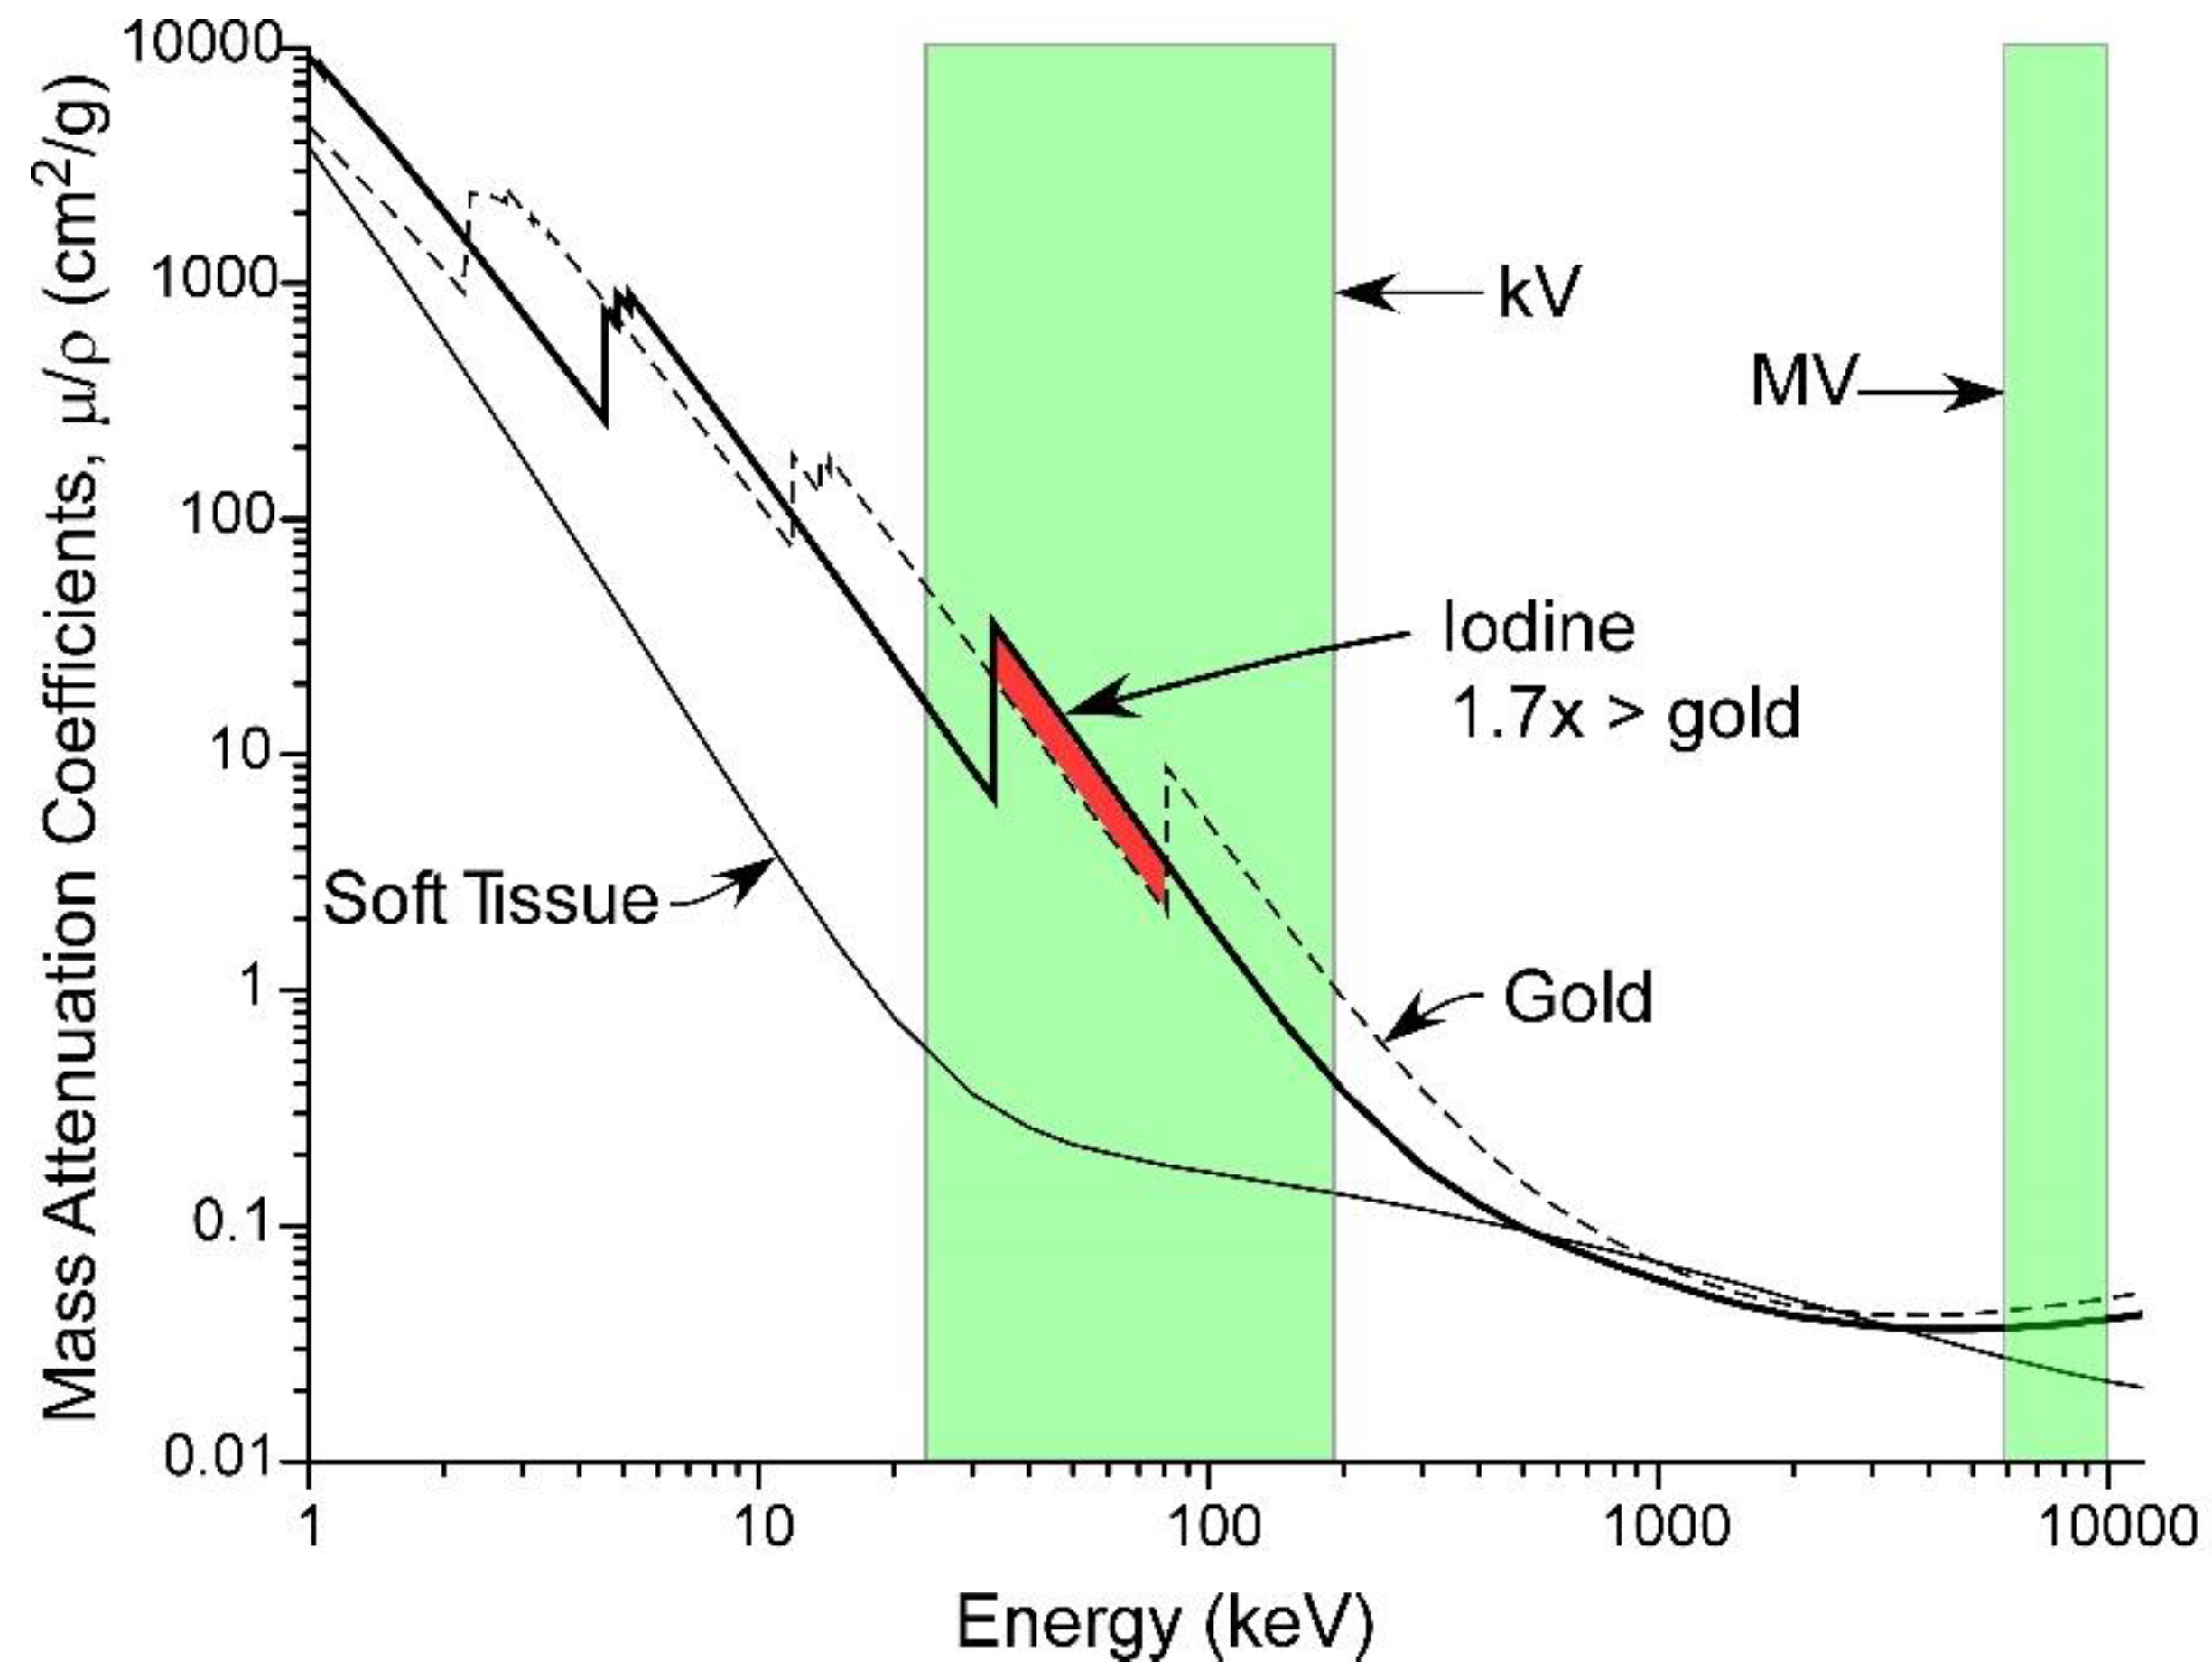

1.1. Mechanism

1.10. Optimal X-ray Energy